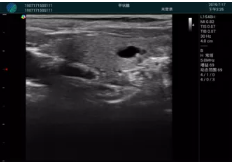

甲狀腺囊性結節(jié),囊壁鈣化,透聲好

甲狀腺囊性占位